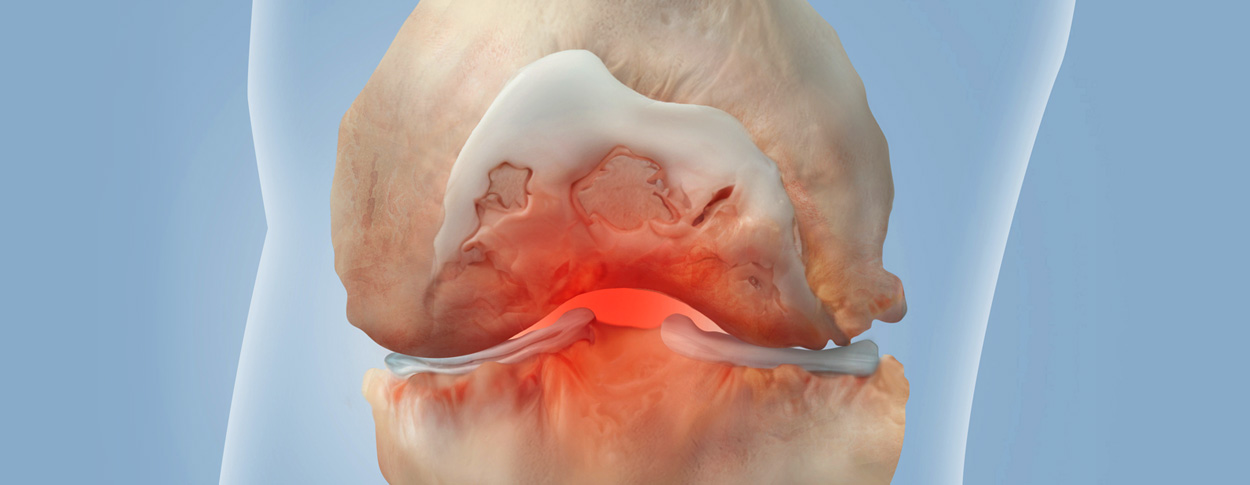

손상된 관절 연골을 재생시켜 관절 기능을 회복하고 통증을 완화하는 치료법입니다.

다양한 연골재생술 기법이 있으며, 환자의 상태와 손상 정도에 따라 적절한 방법을 선택합니다.